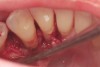

The patient had been referred for an implant consultation for the mandibular right canine. She had very deep probing depths on the lingual. When the flap was raised, a significant amount of subgingival calculus was seen as a local risk factor (Figure 18). However, she had no significant pathology to remove from the situation. Debridement was performed the same as in Case 3 with the rotary ultrasonic and manual instrumentation.

The defect was obturated with mineralized freeze-dried bone and hydrated with platelet-derived growth factor. As with any growth factor, when implementing it clinically, all growth factors require a carrier to bring that growth factor to the desired site, which do not elicit an inflammatory response. In this situation, it is the mineralized freeze-dried bone allograft. This combination was demonstrated by Rosen et al8 to be efficacious in treating intrabony defects. A biologic approach was taken both in terms of the graft and membrane (Figure 19). Primary closure was achieved.

Subgingival calculus and severe bone loss.

Figure 18